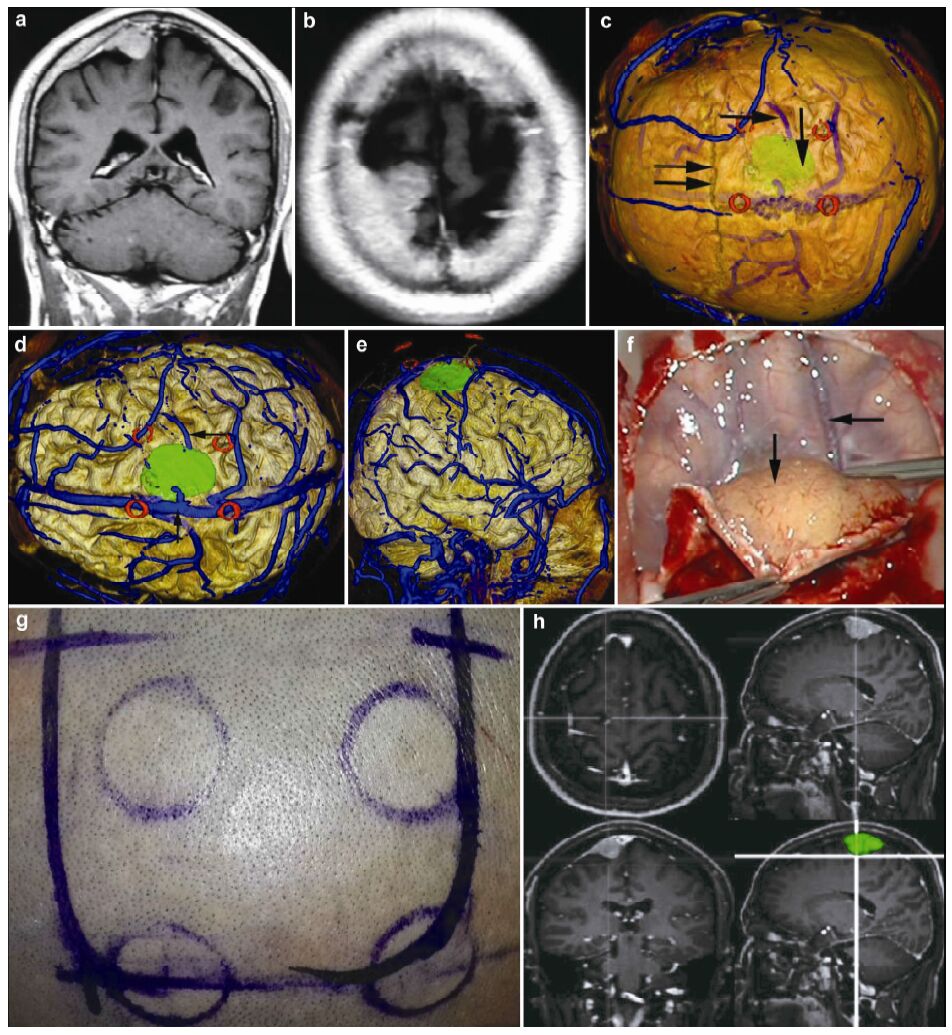

| Figure 1 Magnetic resonance imaging, reconstruction images, surgical incision, and actual operative view in a 51-year-old male patient with a meningioma in right parietal lobe. (a, b) T1 enhancement scans: The tumor presented as homogenous enhancement. (c) 3D reconstruction (skull semitransparent): The tumor (vertical single arrow) located above lambdoidal suture (horizontal double arrow) and the superior cerebral veins (horizontal single arrow) are faintly visible. (d) 3D reconstruction (do not show the skull): On the surface of brain adjacent to the tumor are superior cerebral veins and superior sagittal sinus. (e) Sagittal cutting: The tumor is above the vein of galen and straight sinus. (f, g) The comparison of intraoperative situation and 3D reconstruction: The intraoperative situation is consistent with 3D reconstruction images. (h) Surgical incision. |